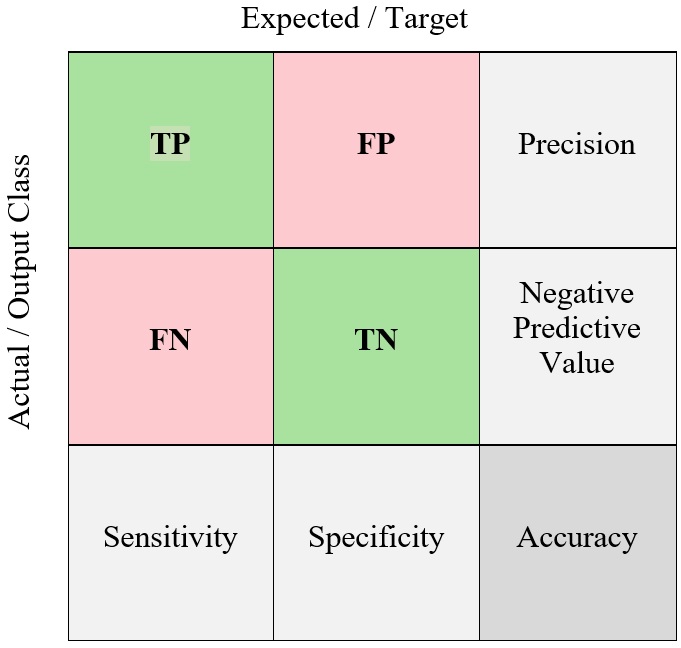

The measurement parameters TP, FP, TN, and FN represent True Positive, False Positive, True Negative, and False Negative percentages, respectively.

Diagnostic testing necessitates a low False Negative (FN) rate or high sensitivity often at the risk of increasing the False Positive (FP) rate.

The effectiveness of each neural network is evaluated with various standard metrics of performance.

These metrics are the accuracy, precision, specificity, recall, sensitivity, and F1- score, False Positive Rate (FPR), and the Area Under Curve (AUC) [28, 29]. These metrics are defined as follows:

These metrics of performance are represented in the confusion matrix that is shown in Figure 5. For medical diagnostic purposes, it is imperative that all positive cases are correctly classified. Therefore, a lower decision threshold is preferred. At each decision threshold, the sensitivity or true positive rate (TPR) as found in Equation (4) is plotted in the y-axis against the ‘average False Positive per image’ or false positive rate (FPR) as found in Equation (6). As the threshold is lowered, both the TPR and FPR increase or remain constant. The area under the ROC curve (AUC) aggregates the performance of the neural network on all decision thresholds. This represents the average performance of the neural network. The closer the AUC is to 1.0, the better the network is at distinguishing between positive and negative classes [28, 29, 36, 37].